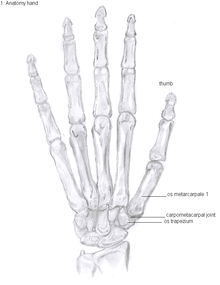

Anatomy

The CMC1 joint is a synovial joint between the trapezium bone of the wrist and the metacarpal bone at the base of the thumb. This joint is a so-called saddle joint (articulatio sellaris), unlike the CMC joints of the other four fingers which are ellipsoid joints.[7] This means that the surfaces of the CMC1 joint are both concave and convex.

This high mobility is due to the little intrinsic osseous stability of the joint. This causes the CMC1 joint to be more unstable compared to the CMC joints of the other fingers.[9] Because of this instability, the joint is more susceptible to be damaged.[10] To remain stable the CMC1 joint has to rely on the surrounding ligaments for support. These ligaments provide the ability to subject high pressure loads, particularly during pinch and grasp manoeuvres.[11]

16 ligaments surrounding the CMC1 joint are identified, which give strength and stability to the joint. Of these ligaments, the deep anterior oblique ligament, also known as the palmar beak ligament, is considered to be the most important stabilizing ligament.[12]